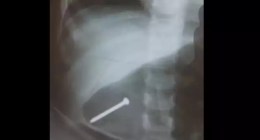

Criança nasce com três braços; médicos consideram a anomalia rara

Embora relatada apenas algumas vezes na literatura médica, a polimelia pode ocorrer quando dois pares de brotos aparecem na superfície de um embrião que se desenvolve em membros e, às vezes, podem ser interrompidos e formar outros brotos